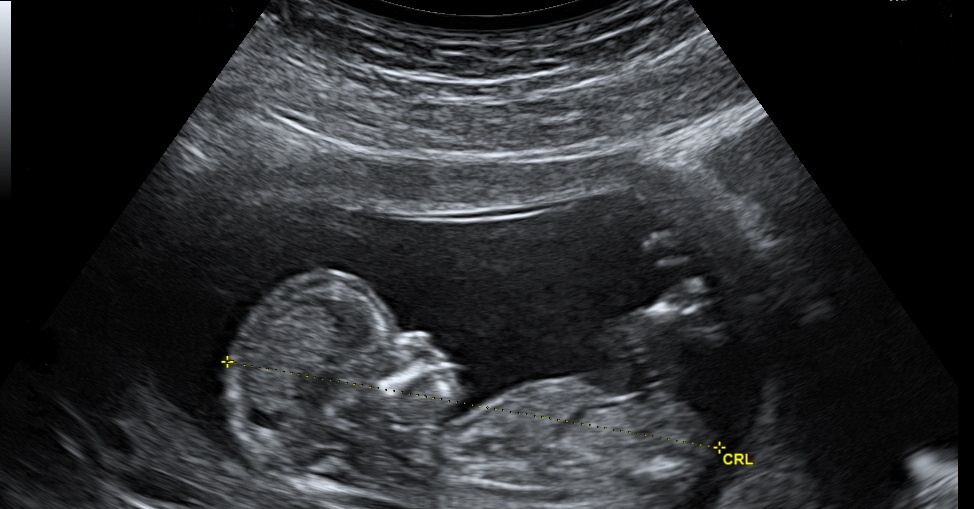

UltraSound

Ultrasound is a type of imaging. It uses high-frequency sound waves to look at organs and structures inside the body. Health care professionals use it to view the heart, blood vessels, kidneys, liver, and other organs. During pregnancy, doctors use ultrasound to view the fetus. Unlike x-rays, ultrasound does not expose you to radiation.

• Your doctor may order an ultrasound if you’re having pain, swelling, or other symptoms that require an internal view of your organs

• An ultrasound can provide a view of the Bladder, brain (in infants), eyes , gallbladder, kidneys, liver, ovaries, pancreas, spleen, thyroid, testicles, uterus, blood vessels

• Preferred method to diagnose complications of unborn babies